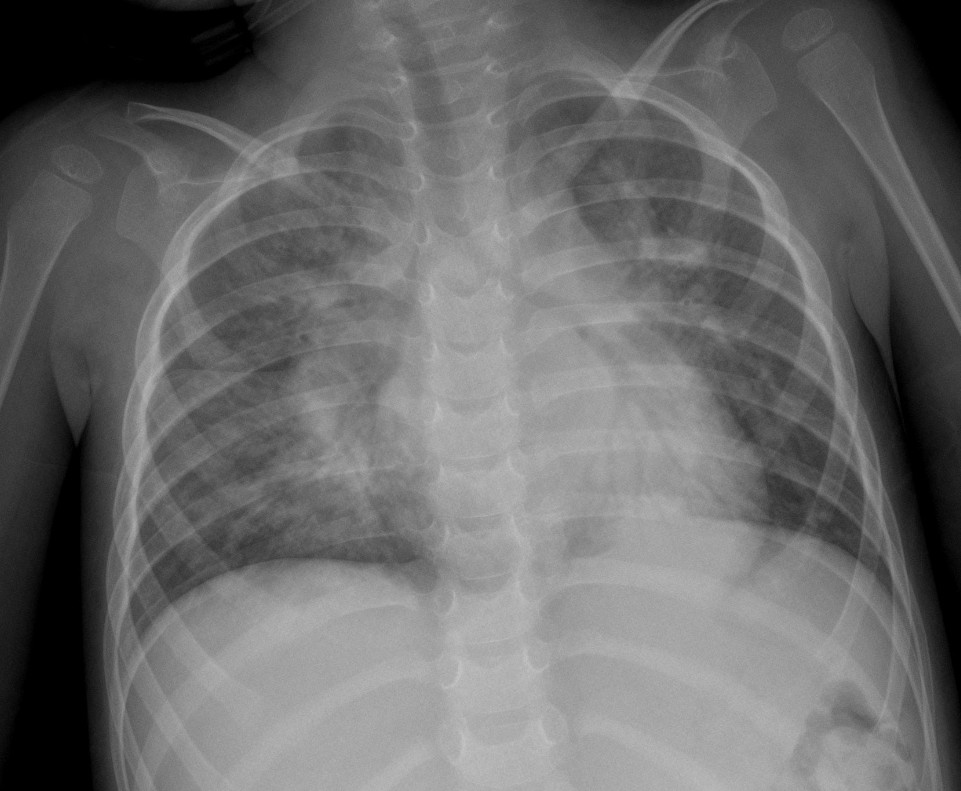

CASO: Febrícula y tos de 4 días de evolución.

Hallazgos:

- En la placa PA se observa una asimetría en los hilios pulmonares, el hilio izquierdo tiene una densidad aumentada.

- Tras examinar la placa lateral se observa un aumento de densidad en la columna que puede ser compatible con una condensación, es el signo de la desnificación vertebral.

SIGNO DE LA DENSIFICACIÓN VERTEBRAL: En la radiografía lateral normal, la densidad de la columna torácica tiende a disminuir desde la parte superior hasta el diafragma; la alteración de ese patrón por la presencia de una densidad superpuesta a la columna, indica la existencia de una consolidación pulmonar. Este signo adquiere especial valor cuando en la proyección posteroanterior la consolidación está oculta en el espacio retrocardíaco o en la base pulmonar.